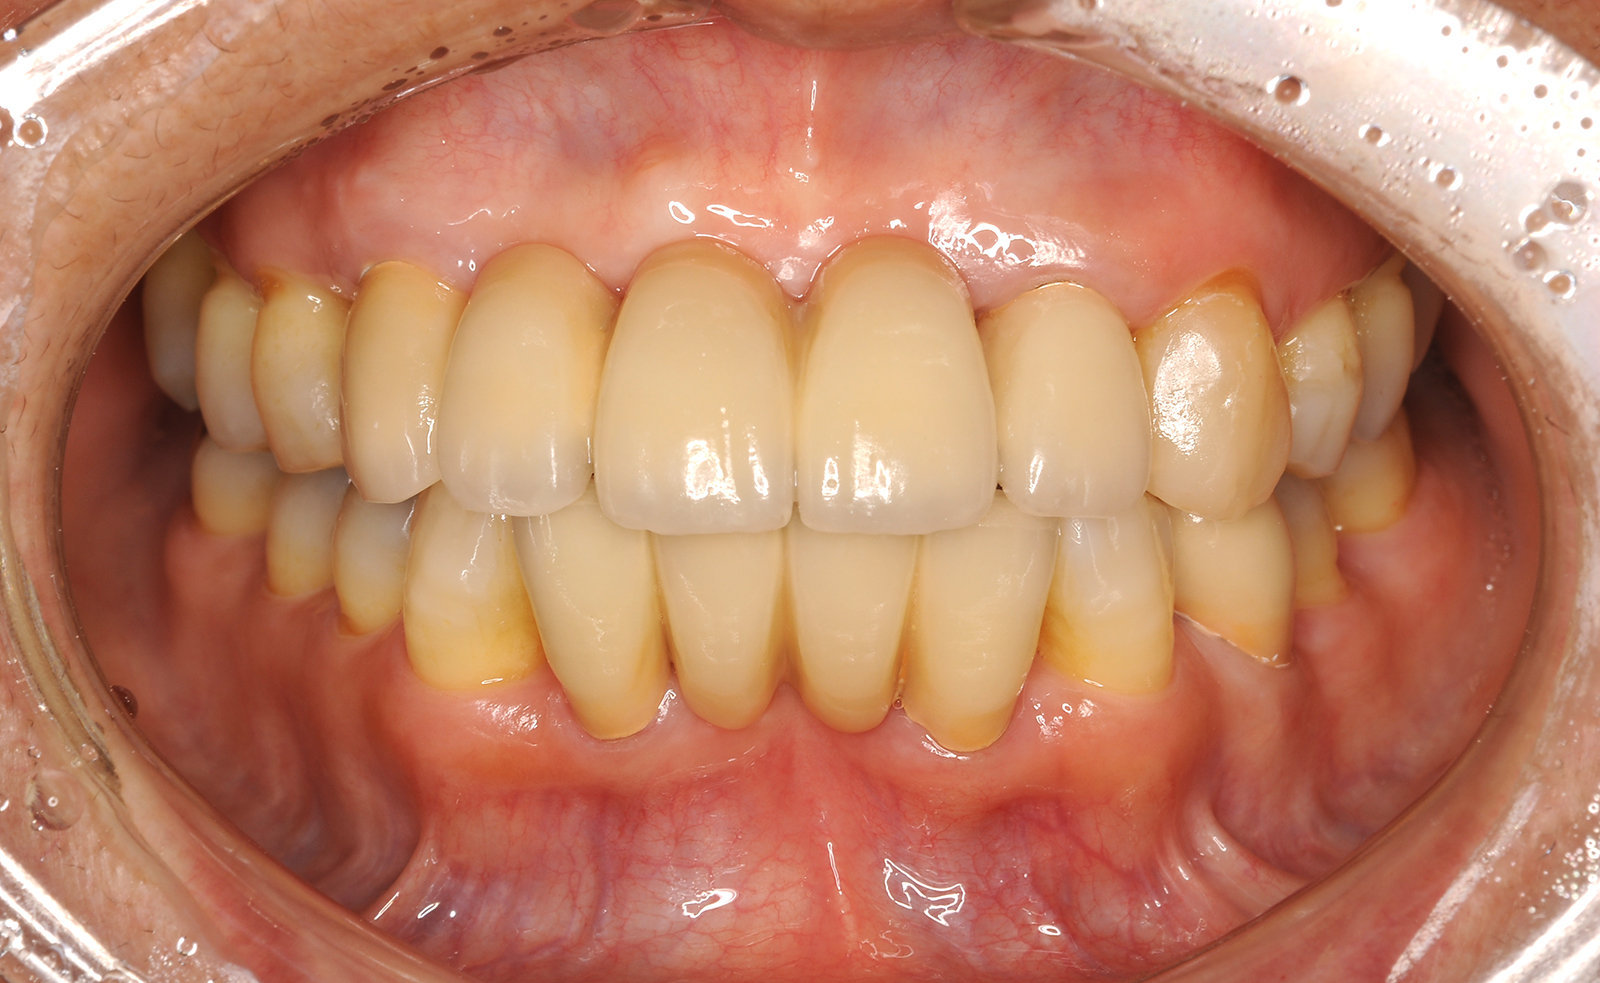

歯周病が進行していくと、歯肉の腫れと退縮が同じタイミングで起こります。治療によって腫れが引きはじめると、歯が長くなった印象を持たれる患者様もいますが、これは歯肉の退縮が原因です。

退縮は見た目の問題だけでなく、本来は歯肉の中にあるべき歯の一部が外に出ているので、知覚過敏などの症状を引き起こすこともあります。当院では退縮で失われてしまった歯肉を外科的に改善する「歯肉移植術」という術式治療を行っています。